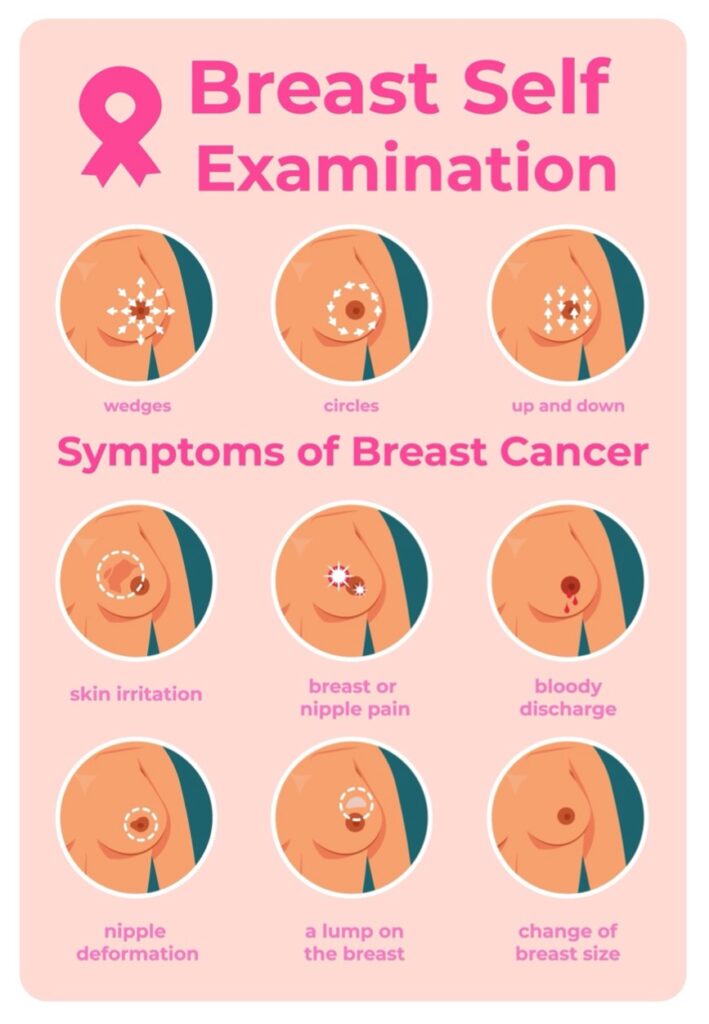

面對乳癌年輕化原因的多樣性,乳癌預防必須從 20 歲就開始建立「自我防護網」。最重要是:建立篩檢習慣:別等痛了才看醫生

很多女性以為「乳房不痛就沒事」,這其實是誤區。早期乳癌通常是不痛的。

- 20 歲起: 每月月經結束後一週進行自我觸摸檢查。

- 30 歲起: 建議每年由專科醫師進行乳房超音波檢查。因為台灣女性乳房組織較緻密,超音波在年輕女性身上的精準度優於 X 光攝影。